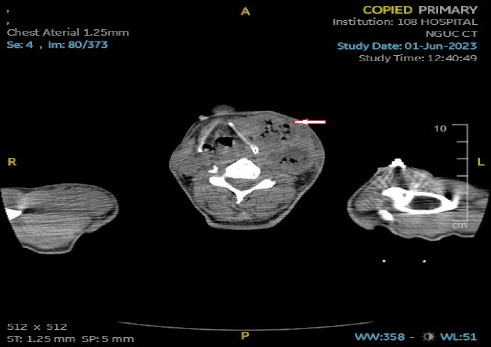

背景:Lemierre's syndrome (LS)是由Andre Lemierre在20世纪初首次描述的,是一种罕见但可能危及生命的疾病,通常由坏死梭杆菌引起。然而,最近的文献报道了由各种其他细菌引起的LS病例,包括肺炎克雷伯菌。在本报告中,我们提出了一例罕见的LS患者与糖尿病引起的肺炎克雷伯菌。病例报告:一名62岁越南男性,有2型糖尿病病史,表现为8天进行性左颈部肿胀、发热、吞咽困难、吞咽困难和食欲下降。尽管最初的抗生素治疗,他的病情恶化,导致肺脓肿和感染性休克。脓肿内容物培养显示肺炎克雷伯菌。患者需要插管、机械通气和颈部脓肿手术引流。美罗培南治疗和血糖控制导致临床改善。患者随后拔管,创面完全愈合,生化指标正常出院。结论:该病例强调了LS可能由Andre Lemierre最初未概述的病原体引起,例如肺炎克雷伯菌。当临床强烈怀疑LS时,临床医生应考虑更广泛的致病微生物,并相应地调整抗菌药物的覆盖范围。肺炎克雷伯菌相关的LS与糖尿病之间的关系值得进一步调查,因为目前的证据表明糖尿病可能使患者易患这种特殊病原体。

Background: Lemierre's syndrome (LS), first described by Andre Lemierre in the early 20th century, is a rare but potentially life-threatening condition typically caused by Fusobacterium necrophorum. However, recent literature has reported cases of LS caused by various other bacteria, including Klebsiella pneumoniae. In this report, we present a rare case of LS in a patient with diabetes caused by K. pneumoniae. Case Report: A 62-year-old Vietnamese male with a history of type 2 diabetes mellitus, presented with an 8-day history of progressive left neck swelling, fever, dysphagia, odynophagia, and reduced appetite. Despite initial antibiotic therapy, his condition deteriorated, leading to pulmonary abscesses and septic shock. Abscess content culture revealed K. pneumoniae. The patient required intubation, mechanical ventilation, and surgical drainage of the neck abscess. Treatment with meropenem, along with glycemic control, led to clinical improvement. The patient was subsequently extubated, achieved complete wound healing, and was discharged with normal biochemical parameters. Conclusion: This case highlights that LS can be caused by pathogens not initially outlined by Andre Lemierre, such as K. pneumoniae. Clinicians should consider a broader spectrum of causative organisms when there is a strong clinical suspicion of LS and adjust antimicrobial coverage accordingly. The association between K. pneumoniae-related LS and diabetes mellitus warrants further investigation, as current evidence suggests that diabetes may predispose patients to this particular pathogen.